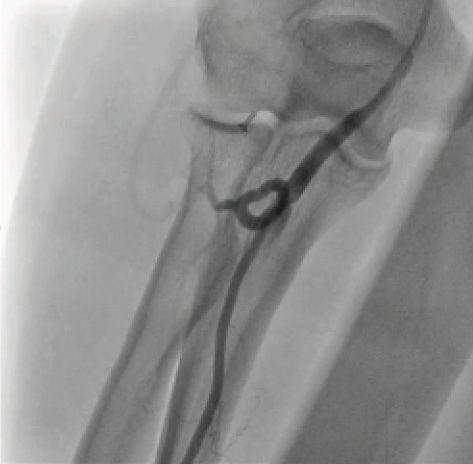

Transradial cardiac angiography and catheterization have been increasingly adopted over the past 10 years in the United States.1 Advantages of this technique include reduced mortality in patients with acute coronary syndrome, decreased vascular complications, shorter length of stay, early ambulation, and the potential for same-day discharge after percutaneous coronary intervention (PCI).2-4 This approach, however, can have a steep learning curve as well as unique hurdles that are not present with a traditional femoral approach. A potential area of difficulty is the anatomic variations that an operator can encounter between the radial artery and the coronary ostia. Radial loops are an uncommon but challenging vascular anomaly (Figure 1). Navigating around this anomaly can be arduous and can lead to conversion to alternative access sites or to complications such as perforation (Figure 2). As a result, the identification of radial loops and the strategies to circumvent them are crucial tools for performing safe and effective procedures via the radial approach in today’s cardiac catheterization lab.